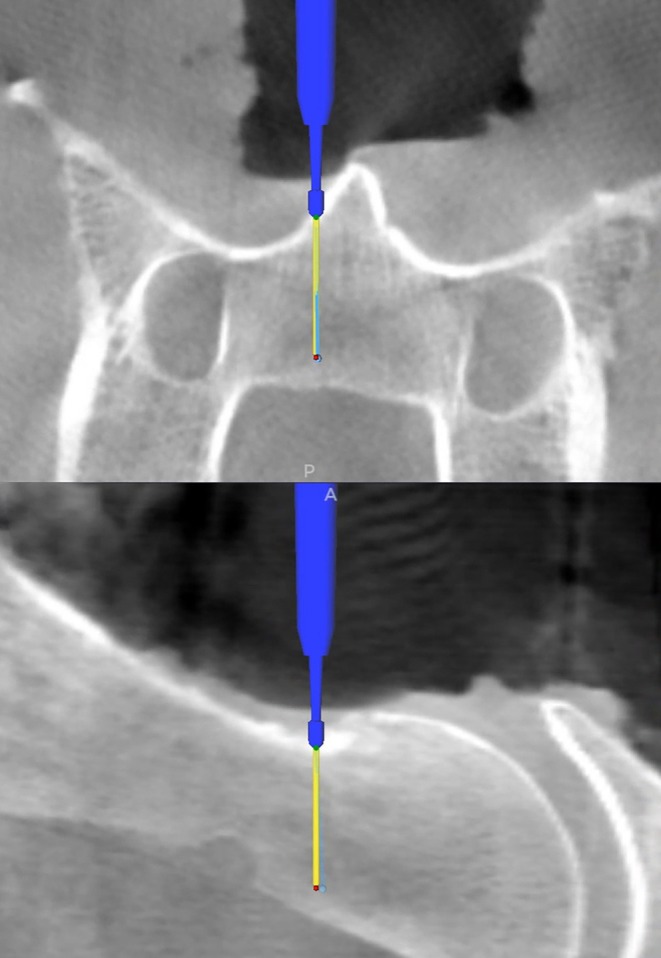

目的:评价计算机辅助马颈椎手术(CAS)使用专用颈椎架(CF)进行颈部稳定的准确性。研究设计:实验性尸体研究。样本人群:6具完整的新鲜马尸体。方法:尸体背部平躺,颈部在CF内伸展。使用基于锥束计算机断层扫描(CBCT)的光学跟踪手术导航系统。腹侧入路暴露颈椎C3-C5。在每具尸体上,将患者追踪器放置在CF(位置CF)上准备12个钻孔通道,然后将患者追踪器放置在C3(位置C3)上准备12个钻孔通道。通过在合并的术前和术后数据集上测量计划和执行的进入点与目标点之间的欧几里得距离来评估手术准确度差(SAA)。描述性统计和重复测量方差分析(rep. mean)。方差分析(ANOVA)比较各组间SAA测量值。结果:患者追踪器位置CF的平均±SD SAA(欧氏距离)为2.00±0.98 mm, C3位置的平均±SD SAA为2.41±1.31 mm。方差分析p = .215)。在钻孔通道最背侧点,患者追踪器位置CF的5/72测量和C3位置的12/72测量发生背腹侧偏移bbbb2 mm。结论:CF允许无限制的术前和术中CBCT成像和计算机辅助钻取近2 mm的SAA。将患者追踪器放置在CF上,手术视野外,不影响手术的准确性。临床意义:CF可促进经腹侧入路马颈椎行CAS手术。

Methods: Cadavers were positioned in dorsal recumbency with the neck extended within the CF. A cone-beam computed tomography (CBCT)-based surgical navigation system with optical tracking was used. A ventral approach exposed cervical vertebrae C3-C5. In each cadaver, 12 drill corridors were prepared with the patient tracker on the CF (position CF), followed by 12 corridors with the patient tracker on C3 (position C3). Surgical accuracy aberration (SAA) was assessed by measuring Euclidean distances between planned and executed entry and target points on merged pre- and postoperative datasets. Descriptive statistics and repeated-measures analyses of variance (rep.-meas. ANOVA) compared SAA measurements between groups.